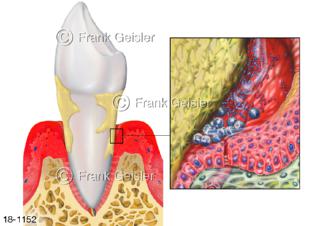

18-1152 Parodontitis Parodontose Zahntasche, chronische Entzündung Zahnhalteapparat